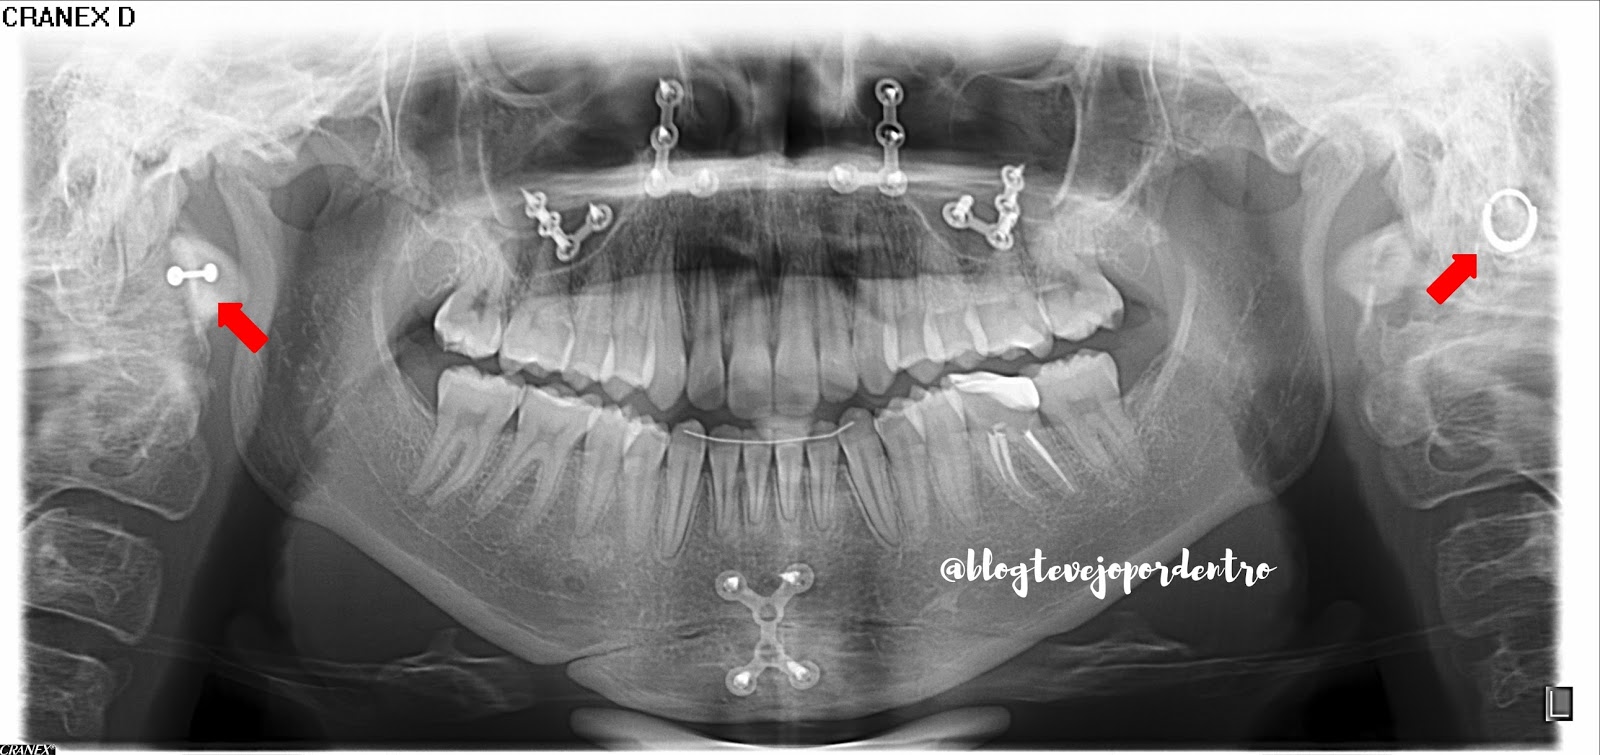

Temos aqui radiografias panorâmica e telerradiografia lateral onde destaco a presença de acessórios de fixação funcional estável na maxila e mandíbula.

E indicados pelas setas vermelhas , piercings que o paciente não removeu para fazer os exames.